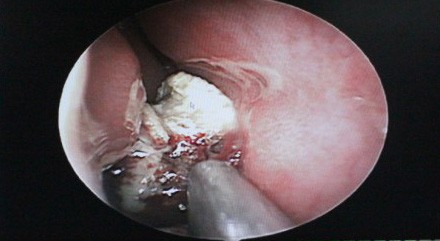

医院接诊医生为小徐做了鼻内镜检查,结果显示:小徐的双侧鼻腔粘膜苍白,双侧下鼻甲肥大,右侧鼻道见一不规则型肿物,质地坚硬,可活动,表面伪膜附着,周边黏脱炎性改变,触之易出血,鼻咽部未见异常。因鼻腔内有未知脓肿,门诊随即将小徐收住入院。

鼻内镜下发现徐小姐右鼻腔内有未知脓肿物存在

经过全面的检查并取得了小徐本人的同意后,医生决定为小徐实施手术。1月5日,手术开始。西安中大耳鼻喉医院耳鼻喉科副主任医师来长荣黄主任在局麻鼻内镜下为小徐进行了右鼻腔肿物切除术,手术中终于见到了那个未知的脓肿,竟然是一块直径约2cm的橡皮异物,由于时间太长,橡皮表面钙化结晶盐形成,堵塞在了下鼻道和鼻中隔之间。在鼻内镜下去除异物之后,黄主任又进行了右侧筛窦开放、蝶窦口扩大术,清理了蝶窦腔内囊肿,后以明胶海绵填塞右侧鼻腔,手术顺利完成。